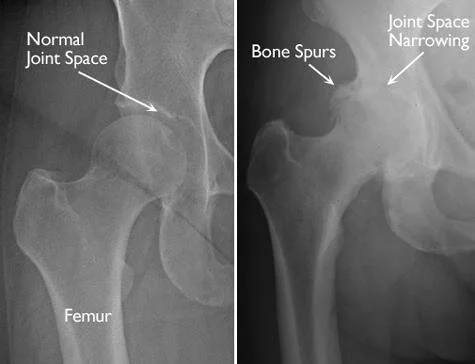

Arthritis is a major cause of hip pain, especially in older adults. The most common type affecting the hip is osteoarthritis, where the cartilage that cushions the joint gradually wears down.

Symptoms may include:

- Stiffness in the morning

- Pain during walking or standing

- Reduced range of motion

Over time, arthritis can make everyday activities like climbing stairs or sitting uncomfortable.